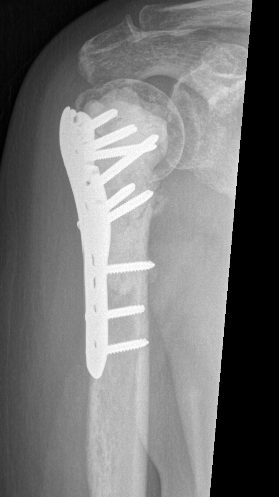

Proximal Humerus

Options

ORIF with plate +/- cement

IMN +/- cement

Tumour prosthesis

Results

Wu et al J Orthop Traumatol 2023

- 45 patients with proximal humerus metastasis

- IM nailing + cement versus plate

- lower blood loss and shorted hospital stay with IMN

- better pain relief with IMN